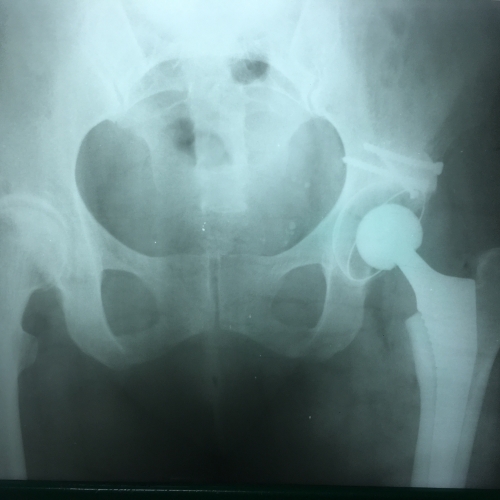

Эндопротезирование тазобедренного сустава